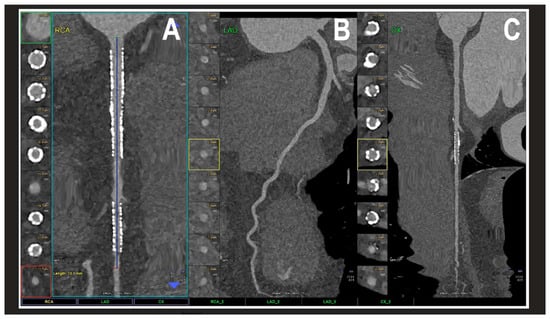

The results regarding PCCT identify it as a revolutionary step in cardiovascular diagnostics. PCCT directly converts X-ray photons into electrical signals, offering a spatial resolution of 0.2 mm2, which is superior to traditional coronary CT angiography [4,15,16,17,18,19] [contribution 11 and contribution 12]. This technical advantage significantly reduces “calcium blooming,” which in turn minimizes the overestimation of coronary stenosis—a common pitfall in conventional CT. Furthermore, PCCT excels in the visualization of coronary plaques, patent lumens, and in-stent restenosis, offering a superior accuracy in quantifying luminal stenosis across all plaque types and characterizing the plaque composition, including its biological activity (Figure 4) [15,16,17,18,19].

Figure 4.

A cardiac PCCT visualization of the coronary stents and stented lumen. There are two stents at the level of the proximal and middle RCA (A) and one stent on the marginal branch of the left LCx (C); the LAD (B) is normal without any detectable atherosclerotic disease. All stents are perfectly visualized in their inner struts and also in their inner lumen, which is difficult to visualize with standard cardiac CT. PCCT—photon counting CT, LAD—left anterior descending, LCx—left circumflex, and RCA—right coronary artery. Reprinted with permission under open access guidelines from Cademartiri et al. [15].

Beyond coronary assessments, this technology enables the precise quantification of the myocardial extracellular volume and the accurate delineation of myocardial scars, which are essential for evaluating perfusion defects. While PCCT is a relatively new technology, its improved diagnostic efficacy is already reducing the necessity for invasive coronary angiography referrals, and future research is expected to uncover an even broader spectrum of clinical applications as the technology becomes more widely implemented. Despite only a few studies published in the JCDD, it is expected that more research will be available on the use of PCCT for CVDs in the near future—when the availability of the technology expands and it is used in many clinical sites—as well as with the increasing experience expected in this research field.